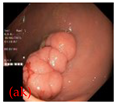

- The Kvasir Dataset: This dataset is publicly available. The KVASIR dataset was released as part of the MediaEval proposed medical multimedia challenge. The dataset is based on images obtained from the digestive tract via endoscopic surgery. The dataset consists of images annotated and validated by doctors and contains 8 different categories. The categories are based on three anatomical landmarks (Z-line, pylorus, and cecum), three pathological findings (esophagitis, polyp, and ulcerative colitis), and two other categories related to the polypectomy procedure (dyeing and lifting the polyp, and dyeing the resection margin). Overall, the dataset consists of 8000 pairs of endoscopic images and masks, with each image measuring 622 × 529 pixels (https://www.kaggle.com/datasets/abdallahwagih/kvasir-dataset-for-classification-and-segmentation (accessed on 15 February 2025)).

As shown in Table 2, AdaptiveConv2d led to more refined handling of segmentation edges on the HAM10000 dataset. Segmentation masks produced by models with standard convolutions often exhibited blurry and smooth edges, neglecting important details and gradient regions. On the Blood Cell dataset, AdaptiveConv2d demonstrated its ability to enhance the segmentation of small target structures. Models without AdaptiveConv2d tended to miss small cells or blur details when processing densely packed cell regions, particularly around cell edges. In contrast, models incorporating AdaptiveConv2d better distinguished each small cell, producing clearer and more complete segmentation results, thereby significantly reducing instances of misdiagnosis or missed diagnosis. This highlights AdaptiveConv2d’s strength in improving fine-grained details when segmenting small objects.

On the Kvasir dataset, the original model’s segmentation results, while capturing the general outline of the target, suffered from inaccuracies in edge and shape details. Specifically, the target area edges were not precisely segmented, leading to “gaps” or “breaks” in some structures (Table 2, ao), particularly in irregularly shaped areas. When dealing with more complex and curved shapes, the original model often missed edges and failed to capture the full target shape. In contrast, the AdaptiveConv2d-enhanced model effectively managed irregularly shaped features, accurately capturing every curve and protrusion. The segmentation results were smoother and more continuous, avoiding breaks and capturing the overall shape of the target more completely.